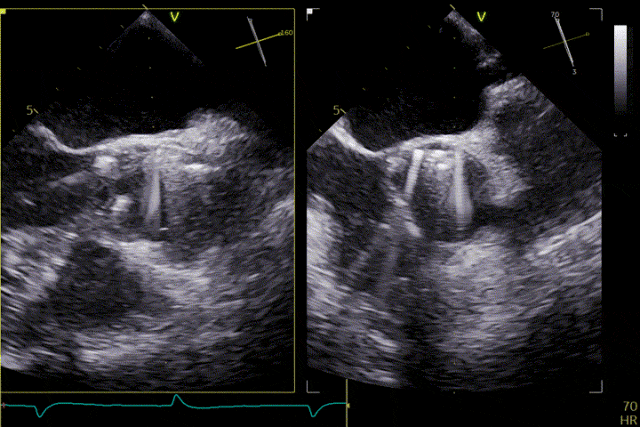

Valve release

Postoperative Outcome

The patient's severe aortic regurgitation was successfully corrected. Postoperatively, there was no residual regurgitation or paravalvular leak. Postoperative echocardiography showed that the bioprosthetic valve had normal opening and closing function, with a mean transvalvular pressure gradient of 2 mmHg and normal flow velocity. The patient demonstrated good recovery, with a significant improvement in cardiac function compared with the preoperative status.